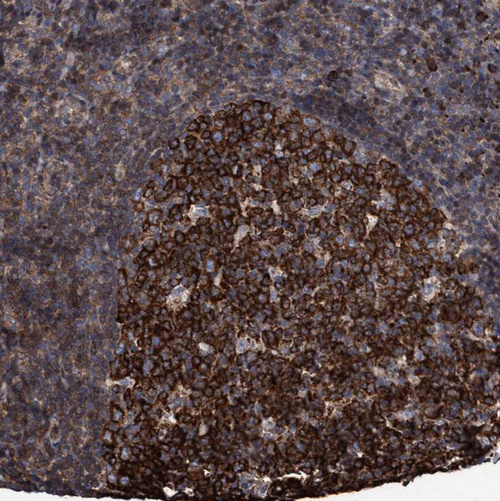

Immunohistochemical staining of human Tonsil shows strong cytoplasmic positivity in germinal center cells.